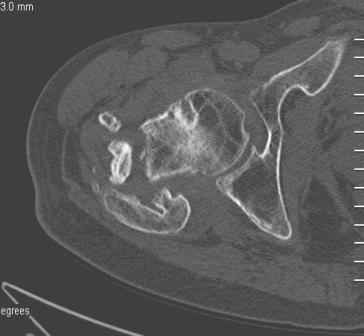

Больной Н. 44 года травма 1,5 года назад июнь 2008 года чрез-под вертельный перелом правого бедра. Во время лечения у больного развился алк. делирий, проводилось консервативное лечение перелома.

Беспокоят боли, укорочение конечности.Укорочение 3 см. Ногу поднимает, сгибание ограничено, ротационные движения в полном объеме.На КТ перелом сросся за счет костной мозоли.Что делать?

Уважаемый Глеб, боли из-за ложного сустава шейки бедра. Сращения там нет.

Уважаемый Глеб! Укорочение наверное побольше, да и наружно-ротационная установка скорее всего присутствует. Суставная щель прекрасная, головка живее всех живых. Ратую за подвертельную с латерализацией: исключает нарушение механической оси («исключает вальгус в коленe»), максимально удлиняет без натяжения m.iliacus. Для иллюстрации остеотомия-переделка (слава богу не автопеределка) у мужчины 65 лет.